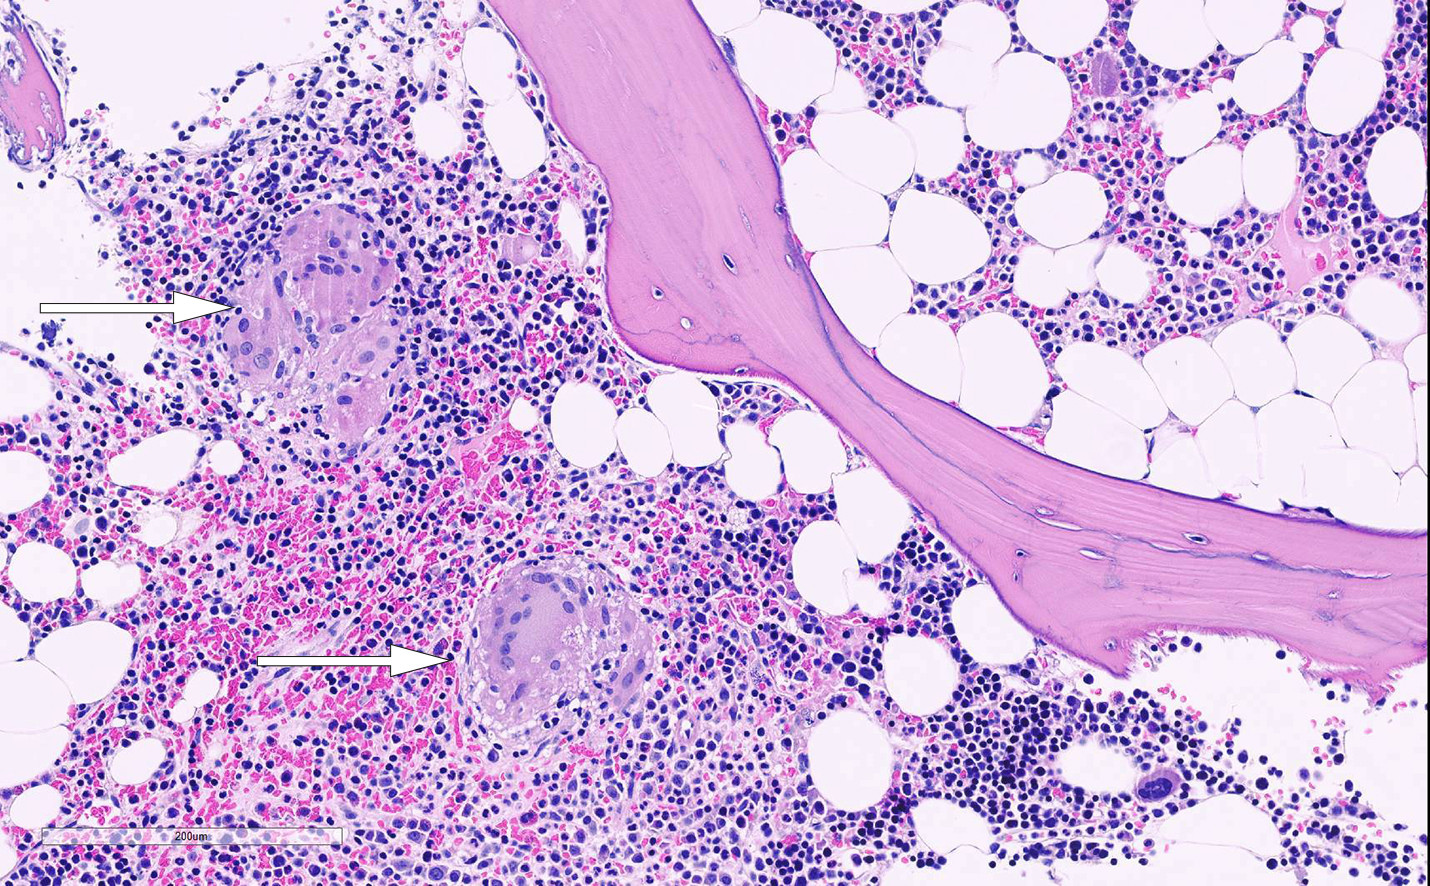

Åtte uker etter svar på beinmargsbiopsi ble pasienten undersøkt med 18F-FDG-PET/CT. Undersøkelsen viste økt opptak av 18F-FDG relatert til magesekk og høyre colonfleksur. Funnet kunne passe med gastrointestinal manifestasjon av sarkoidose. Koloskopi tre uker senere viste makroskopisk normale funn, og biopsier viste lette reaktive forandringer. Ved gastroskopi var det funn av minimalt prepylorisk erytem, for øvrig makroskopisk normale funn i duodenum. Det ble likevel gjort duodenalbiopsier, og disse viste kronisk betennelse med intraepitelial lymfocytose og subtotal totteatrofi. Det var ikke funn av granulomer (figur 3). Blodprøver verifiserte sterkt positivt funn av IgA-antistoffer mot transglutaminase 2 (anti-TG2) med titer > 250 U/ml (< 14,9), lave jernlagre med ferritin på 11 µg/l (18–240). Vevstyping påviste HLA-DQ2, som er assosiert med cøliaki. Funnene var vurdert forenlig med cøliaki (ramme 2), selv om det anamnestisk ikke forelå gastrointestinale symptomer. Cøliakidiagnose ble satt tre måneder etter første kontakt ved medisinsk poliklinikk. Hun ble anbefalt å legge om til glutenfritt kosthold. Samtidig startet hun tverrfaglig rehabilitering, som fastlege hadde henvist til.

Funn ved PET/CT førte til mistanke om patologi i gastrointestinalkanalen, og gastroskopifunn med biopsering sammenholdt med positiv serologiprøve og påvist vevstype HLA-DQ2 gjorde at vi kunne stille diagnosen cøliaki (20). Vår pasient oppfylte fire av fem diagnostiske kriterier (ramme 2).

Cøliaki er en glutenindusert, systemisk, autoimmun sykdom (20, 21). Sykdommen blir diagnostisert både hos barn og voksne (20, 22). Det er i senere tid rettet større oppmerksomhet mot ikke-gastrointestinale symptomer og assosierte lidelser ved cøliaki (21). Studier viser at ekstra-intestinale manifestasjoner er meget vanlig (21, 22), inkludert symptomer som kan ligne revmatiske sykdommer (21). Sarkoidose og cøliaki er assosiert med bestemte vevstyper, HLA-DR3 og HLA-DQ2 (23, 24), der sistnevnte forelå hos vår pasient. En assosiasjon mellom disse to lidelsene finnes trolig (23, 24), og flere har foreslått å screene for cøliaki hos pasienter med sarkoidose (25). Det er også mulig at sykdommene predisponerer for hverandre ved at uttrykket av HLA økes (23). Det er en kjent sammenheng mellom ubehandlet cøliaki og intestinale kreftsykdommer, spesielt B- og T-cellelymfom.